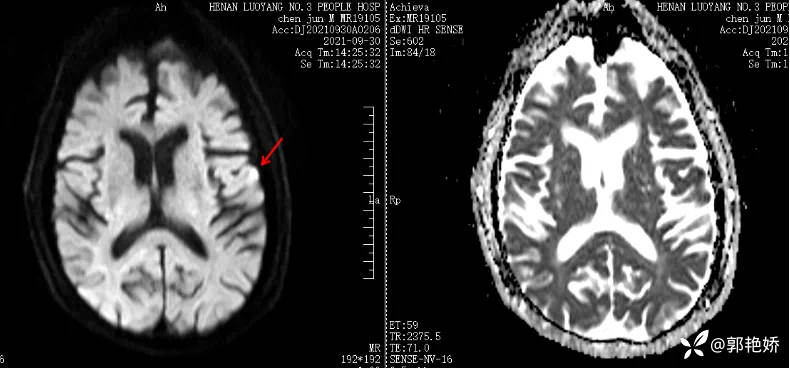

头颅核磁如图1a、1b:

图1:左侧额叶点状梗死灶

复查头MRI如图2a、2b:

图2:左侧额叶及半卵圆中心散在急性梗死灶